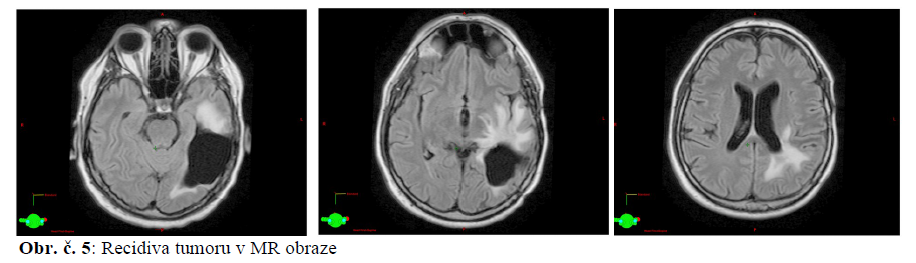

25.6. 2013 MR mozku: oproti lednu 2013 výrazná progrese obrazu- tkáňová masa 40x20x30mm podél trigona levé postranní komory nad a mediálně od poresekční likvorové dutiny, progreduje i edém.

15.5.2014 MR mozku: výrazná multilokulární recidiva tumoru v okolí resekční dutiny vlevo temporálně a nově i na spodině 4. komory, šířící se do pravé mozečkové hemisféry.